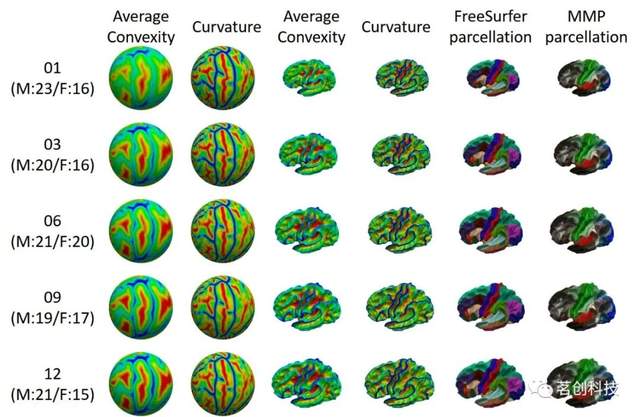

UNC 4D婴儿皮层表面图谱

这是一组具有年龄代表性的时空皮层图谱,包括1、3、6、9、12、18、24、36、48、60和72个月的实足年龄,来自50名健康婴儿的339个纵向MRIs扫描。分割图包括和基于HCP多模式的分割。突出的特点是表皮层图谱在所有年龄段都具有顶点到顶点的皮层对应关系,这允许进行横向和纵向分析。

来源:Construction of 4D high-definition cortical surface atlases of infants: methods and applications.